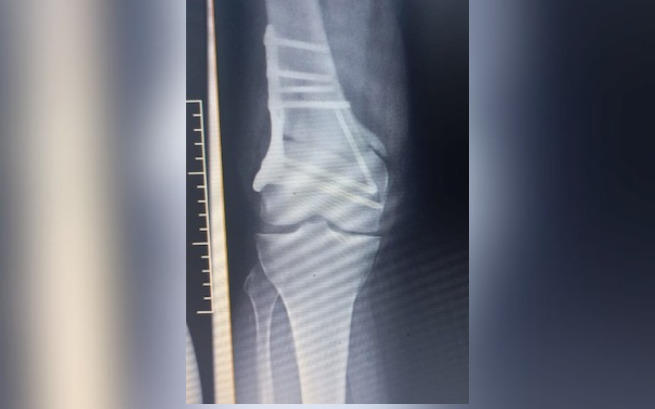

Przed nami kolejne leczenie, zabiegi, operacje, konsultacje ze specjalistami oraz dalsza diagnostyka. Ostatnia reoperacja (17.05.) odbyła się planowo. Po wcześniejszej operacji (22.03.) w dalszym ciągu pozostały poważne komplikacje w postaci braku zrostu w kości udowej. Co więcej, od strony zewnętrznej zespolenie zsunęło się, co konfliktuje z maziówką w wyniku czego ponownie wbijają się w nogę trzy gwoździe, powodując okropny ból.

Tak było kolejny raz z ostatnia operacją Patrycji (22.03), która niestety zakończyła się dużymi powikłaniami. W ich wyniku doszło do silnego zakażenia oraz pęknięcia kości udowej. Kiedy nasza przyjaciółka uporała się z zakażeniem, to okazało się, że kawałek ostrej śruby przedostał się poza kość i rani jej tkanki miękkie.

Patrycja choruje na nowotwór błony maziowej stawów i spondyloartropatię o ciężkim przebiegu z zajęciem całego kręgosłupa oraz wszystkich stawów obwodowych. Obecnie jest już po dziesięciu poważnych operacjach i pięciu zabiegach termolezji, jak i licznych blokadach. Choroba w nieprzewidywalny sposób atakuje kolejne partie jej ciała!

Obecnie Patrycja zmaga się z licznymi powikłaniami po operacji nogi wykonanej w ramach NFZ w sierpniu 2022 roku. Operacja z niewiadomych przyczyn - została wykonana tylko częściowo, niezgodnie z wcześniejszymi zaleceniami, wynikającymi ze skierowania. Po ostatniej konsultacji i diagnostyce okazało się, że noga ta wymaga natychmiastowej reoperacji oraz rekonstrukcji, aby można ją było uratować.